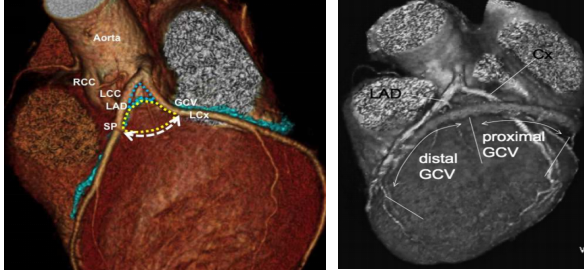

该技术操作极其精细复杂,术者需先将一根细如发丝的导管,经动脉逆行送入心脏的冠状静脉;通过冠状静脉造影,找到为室早病灶供血的微小血管;随后,将少量无水酒精精准注入该血管,造成病灶区域的化学性坏死,从而达到根治心律失常的目的。